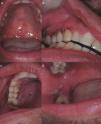

On D+218 (10/6/2016), the patient attended the dental outpatient department complaining of odynophagia and the physical examination revealed multiple clustered and isolated ulcers with irregular and raised borders on the soft and hard palate on the right side, on the right buccal mucosa and on the gingival margin of the right retromolar trigone area. In addition, there were areas of erythema and gingival overgrowth of fibrous consistency, with areas of necrosis on the upper right gingival margin on the palatine surface. The upper gingival margin on the vestibular surface was dark red in color, extending from the canine to the second molar area (Figure 1). The lesions on the free gingival margins exhibited a punched-out aspect (Figure 1B). The other areas of the oral cavity were intact; the patient presented good oral hygiene and good salivary flow (sialometry=0.96mL/min). The patient did not present skin lesions on the face.

(A) Ulcers with irregular and raised borders on the soft palate. (B) Ulcers with irregular and raised borders on gingival margin and areas of erythema and increased gingival volume of fibrous consistency with areas of necrosis. (1) Ulcers with irregular and raised borders on hard palate and gingival margin. (D) Ulcers with irregular and raised borders on the right cheek mucosa.